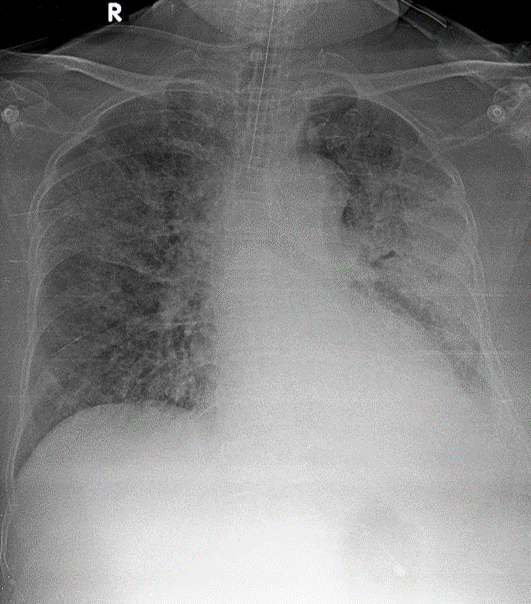

1-Thâm nhiểm phế nang lan tỏa hai phổi=> Viêm phổi 2-Tràn dịch màng phổi (T) 3-Có ống thông nội khí quản